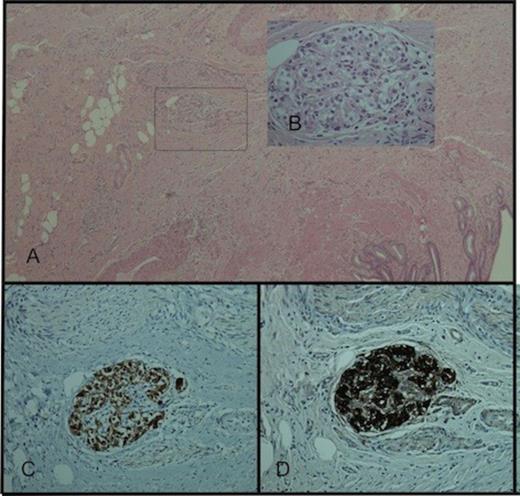

Further investigations included 24-hour urinary catecholamines, which were negative on two occasions. MRI showed no evidence of further disease and six months later, CT scanning showed no evidence of recurrence. As the patient had ongoing right upper quadrant pains, an elective cholecystectomy was performed. Gallbladder histology showed features of chronic cholecystitis. In addition, within the wall was a small (<1mm) nodule of polygonal cells arranged in small nests surrounded by a single layer of thin delicate spindle cells [Figure 4]. Appearances and immunohistochemistry were consistent with a paragangliomatous rest. The patient is well with no evidence of recurrence three years following surgery.

(A) Paraganglion cell rest within the gallbladder wall. H&E staining ×40, (B) H&E staining ×400, (C) synaptophysin immunostaining ×200, (D) chromogranin immunostaining ×200